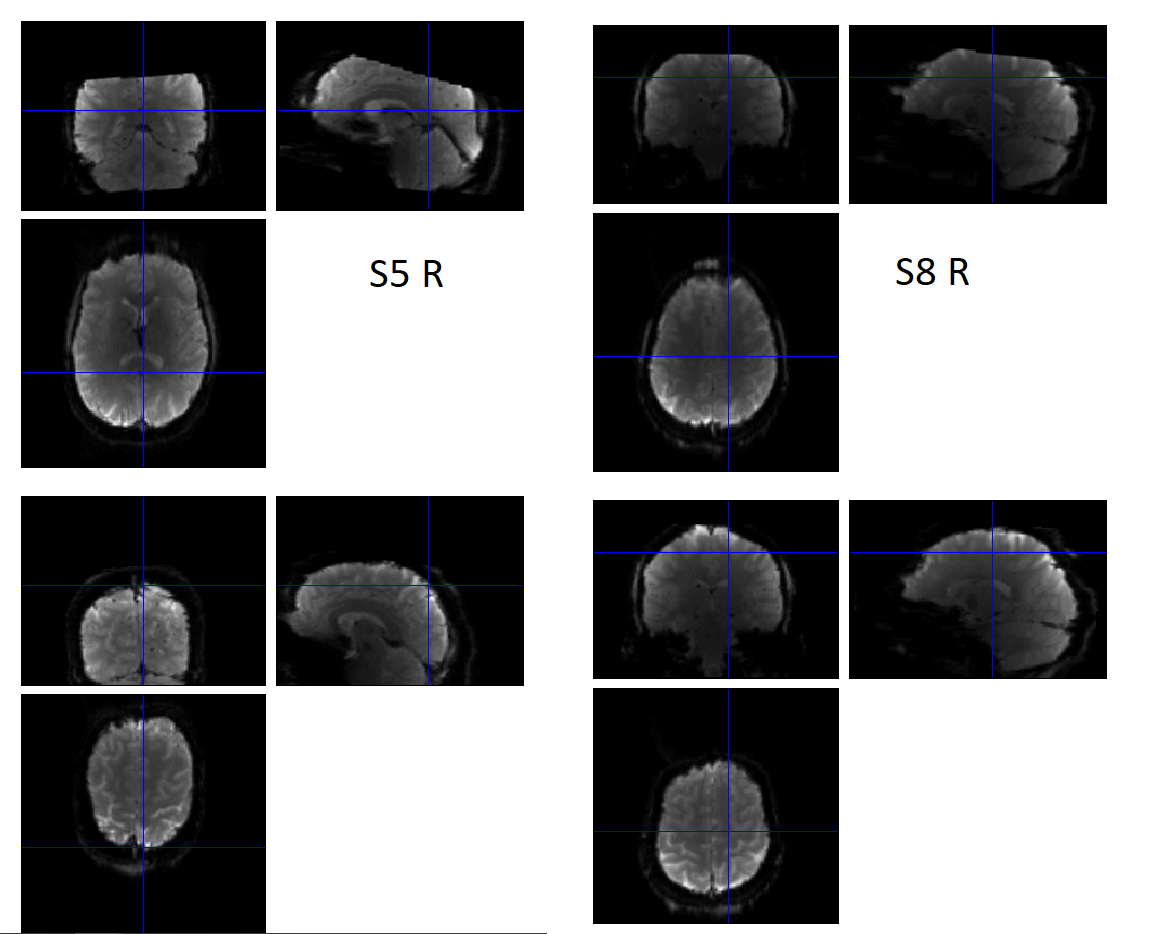

To keep it short, in some subjects, this step fails and produces bad realignments... In fact for some subjects, it's quite bad, with the upper part of the brain being completely cut (see attached file, top realigned, bottom original). Once I re-run the preprocessing, without actually changing anything (from the same starting files), it can produce different results, and in fact work properly...

Interestingly, the "fail" in the realignment doesn't always happen for the same subjects. For example task 1, initially it produced bad results for subjects, 2, 3, 8, and 10. Whereas for task 2, for 5 and 15.... Moreover, I already confirmed that repeating this, from the beginning for subjects 5 and 15, worked normally (as in Realign&unwarp produced good results).